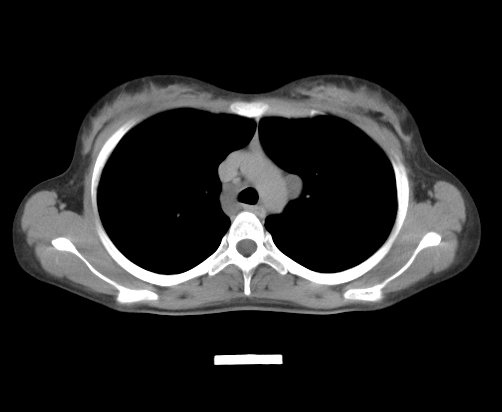

胸部